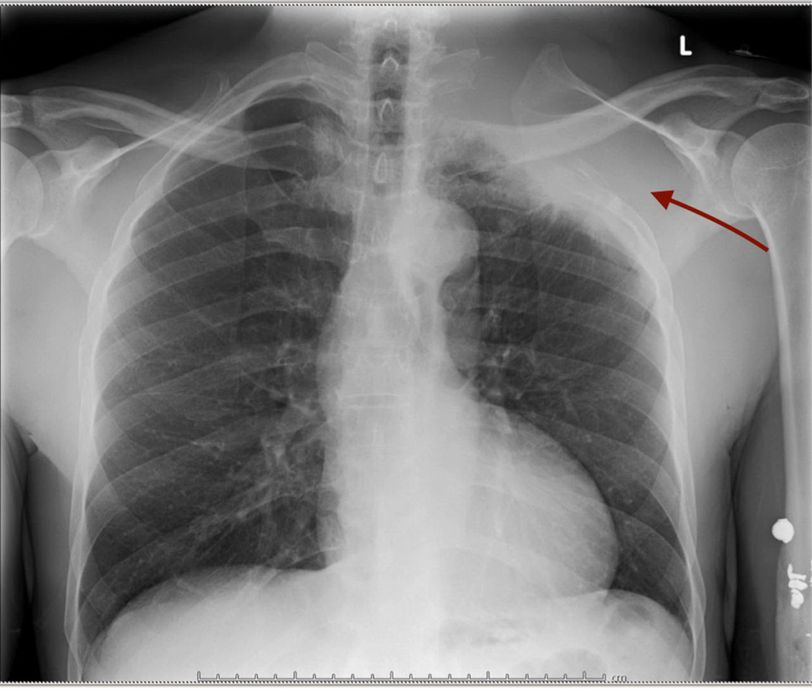

Diagnosis?

Winging of scapula due to paralysis of serratus anterior